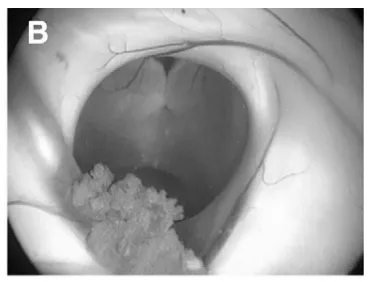

采用先行神经内镜第三脑室造瘘(B-F内镜下视野),再行开颅肿瘤切除的方案,具体过程如下:

(B)室间孔(Monro孔),选择可同时抵达第三脑室底及肿瘤的手术入路